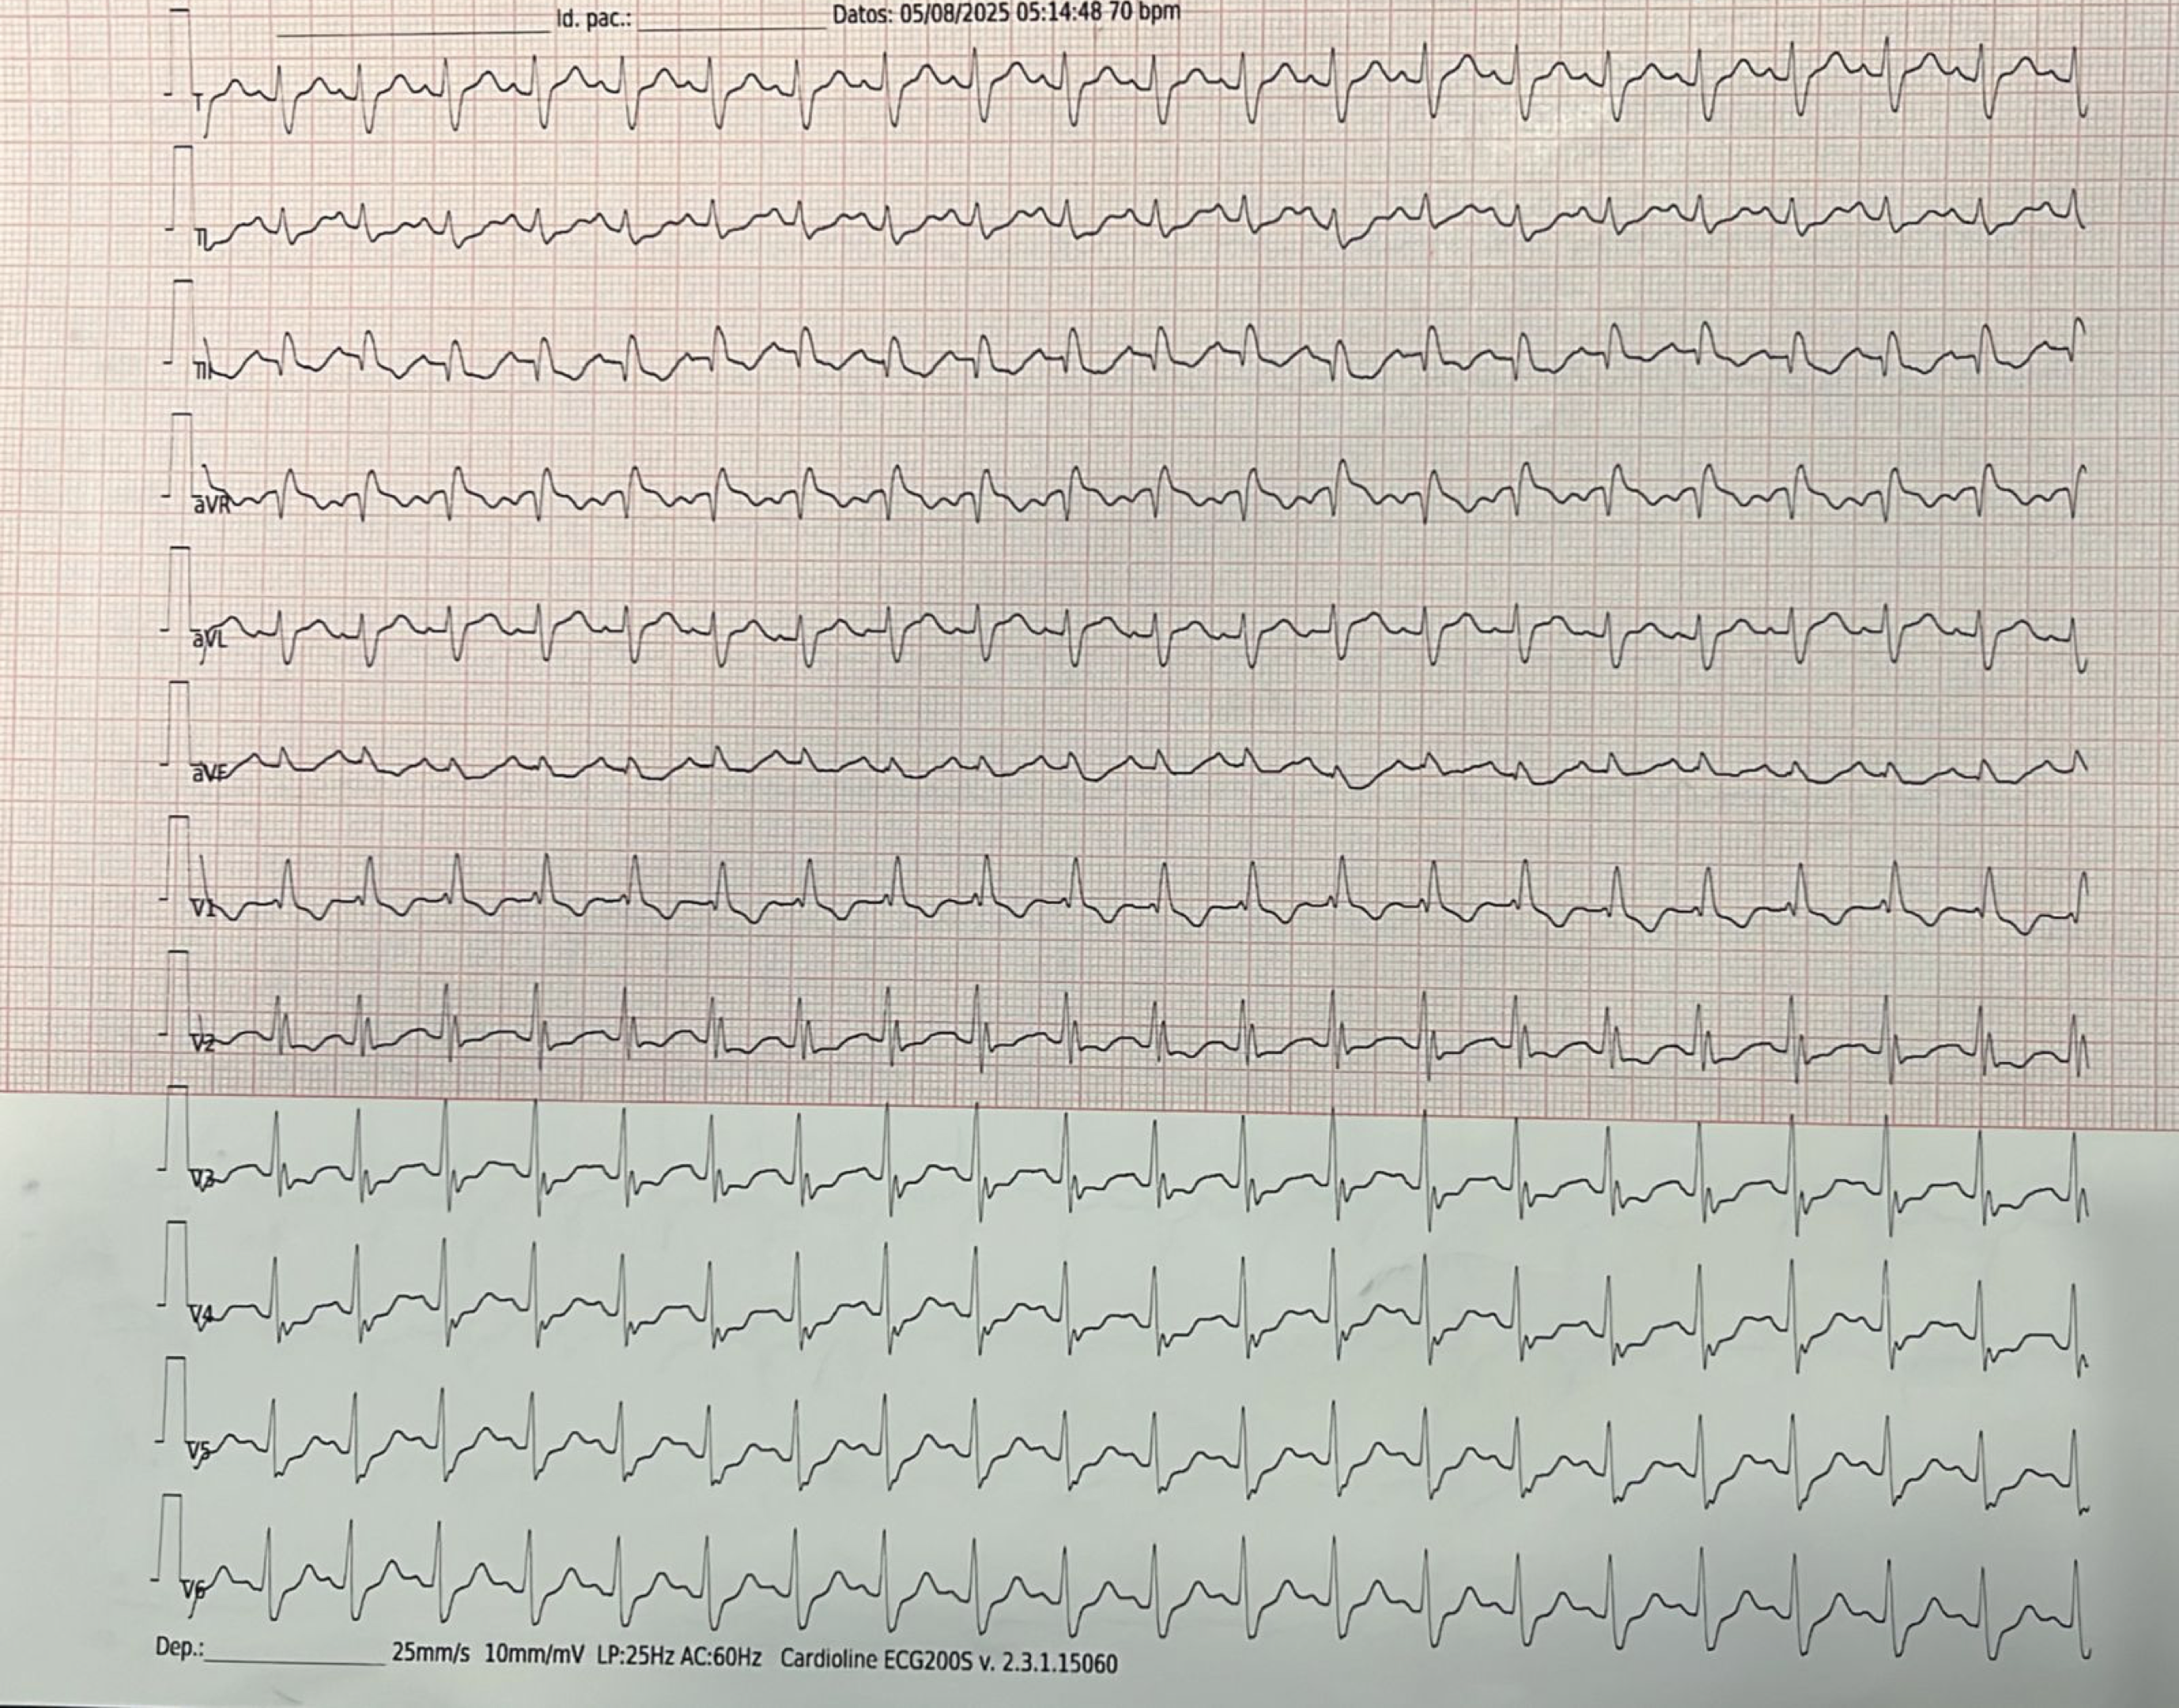

Con este material deberíamos ser capaces de poder realizar el abordaje inicial esta paciente, que se presenta al Servicio de Urgencias con motivo de consulta: Síncope.

Y también deberíamos poder abordar a este paciente: